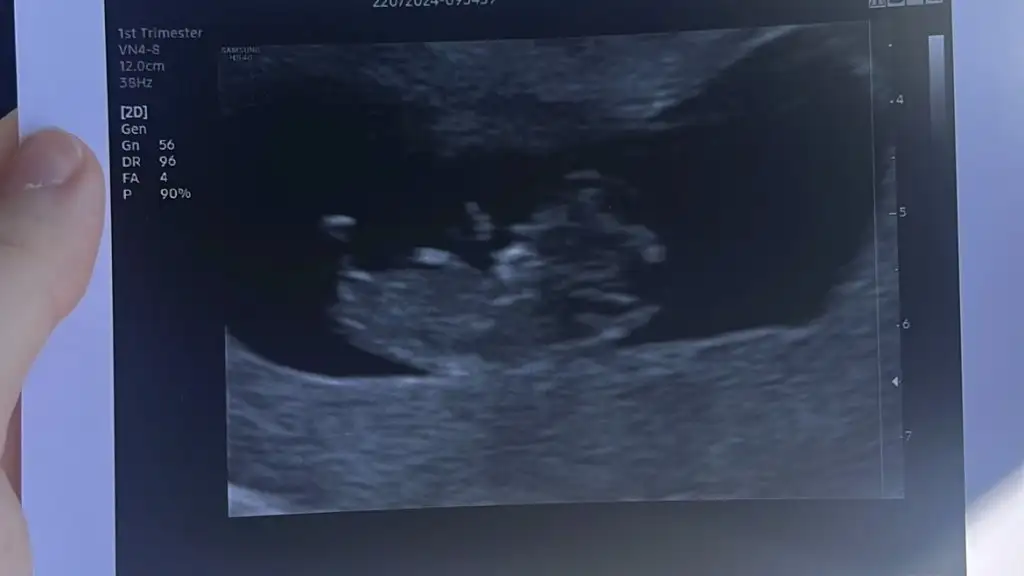

5 ve 14. haftaya kadar olan ultrason fotolarınızı paylaşın. Vajinadan mı yoksa karından mı çekildiğini ve kaç haftalık olduğunu da mutlaka belirtin.